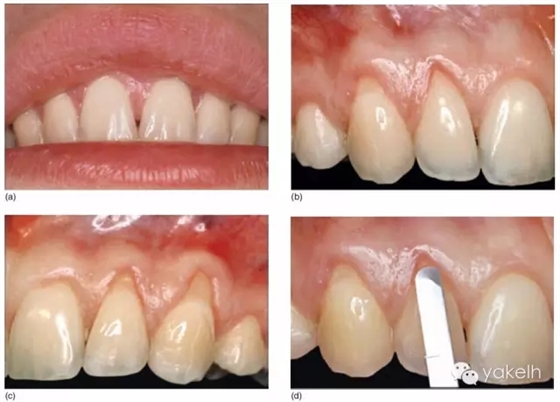

¤¤這類復雜的膜齦手術用于同時處理多個根面Ⅰ類/使Ⅱ類牙齦退縮(圖5.11a~m)。

圖5.11 (a)患者休息放松狀態(tài)下的嘴唇——上下唇不能完全閉合。(b)右上尖牙和側(cè)切牙呈Ⅰ類牙齦退縮。(c)左上頜尖牙和側(cè)切牙呈Ⅱ類牙齦退縮。(d)先用圓形眼科刀片開始做溝內(nèi)切口。(e)使用探針在袋內(nèi)垂直探查貫通隧道,越過膜齦聯(lián)合。(f)使用探針在隧道內(nèi)橫向探查貫通,保留齦乳頭尖端附著于骨面。(g)從腭部取結締組織移植物,使用絲線牽引,將厚度和大小足夠的結締組織瓣插入隧道內(nèi)。(h)通過懸吊縫合將組織瓣冠向復位,穩(wěn)定結締組織瓣。(i)術后6個月,上頜右側(cè)觀。(j)上頜左側(cè)觀,可見牙齦厚度以及色澤的協(xié)調(diào)性均得到改善。(k)術后6個月正面觀,牙敏感癥狀消失。(l)術后1年的全口影像,顯示雙側(cè)的牙齦退縮均被完全覆蓋,牙齦邊緣增厚且穩(wěn)定,與釉牙骨質(zhì)界輪廓一致,也與左側(cè)中切牙釉質(zhì)缺損輪廓一致。(m)患者嶄新的笑容,可見側(cè)切牙及尖牙的齦緣無退縮。